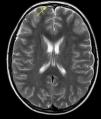

A las 48 h, se realiza una RMN cerebral y medular, donde a los hallazgos de la TC se añade absceso epidural derecho, con colección frontal izquierda purulenta en el espacio subaracnoideo (fig. 4). Ante la ausencia de neurocirugía en nuestro centro, se remite al hospital de referencia, donde se decide actitud conservadora, añadiendo al tratamiento heparina subcutánea. Evolución favorable, con mejoría de las lesiones en la RMN de control, siendo dado de alta a los 15 días, completando tratamiento antibiótico por vía oral hasta 9 semanas con ciprofloxacino dada la buena penetración de este fármaco.